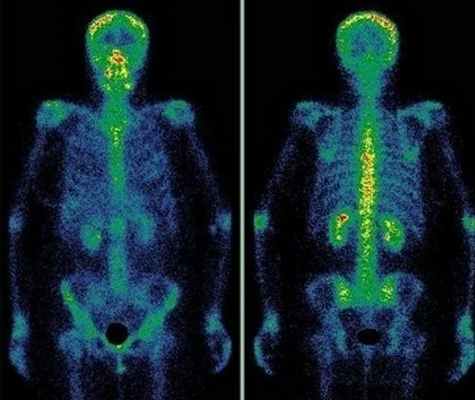

(Справа) Сопоставимая МРТ, аксиальная проекция, режим Т2 с подавлением сигнала от жира: у этой же пациентки через 16 месяцев визуализируются значительные изменения патологического очага. Увеличившееся новообразование характеризуется более выраженной центральной оссификацией и более периферической гиперинтенсивной дольчатостью. Полностью сопоставимые изображения получить трудно, однако исследование в целом позволяет достоверно визуализировать патологический очаг. (Слева) Сцинтиграфия в ПЗ проекции: визуализируется патологическое накопление в области очага, однако это ожидаемый признак при энхондроме.

о Динамическое контрастирование может повышать шансы на успешную дифференциальную диагностику энхондромы и ХС низкой степени злокачественности5. Сцинтиграфия:

• Энхондрома, имея небольшие размеры, характеризуется, тем не менее, повышенным накоплением при сцинтиграфии (>30%)

• Выраженность накопления не имеет прогностического значения относительно дегенерации6. Биопсия под визуальным контролем: